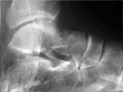

Hand_perilunate_dislocation